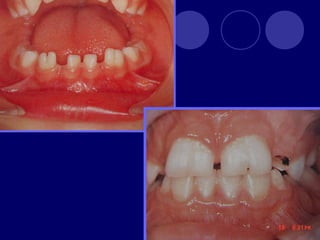

ANOMALÍAS DE NUMERO AGENESIA  SUPERNUMERARIO ( hiperdoncia)

AGENESIA  Falta dedesarrollo de los gérmenes dentales.

ETIOLOGÍA  Obstrucción físicao interrupción de la lamina dental (Sx. Orodigitofacial)  Anomalías funcionales del epitelio dental (displasias ectodérmicas)  Límite de espacio  Falta de inducción del mesénquima

Femenino Permanente=1.6/9.6% Temporal=0.1/0.9% Terceros molares, lateralessuperiores, 2 premolares inferiores, 2 premolar superior, incisivo central inferior Lateral superior, centrales y laterales inferiores.

 ANODONCIA: ausenciatotal de los órganos dentarios.  AGENODONCIA: temporales  ABLASTODONCIA:permanentes  OLIGODONCIA: ausencia de algunos dientes.  OLIGOGENODONCIA: =/- a 10 temporales  OLIGOBLASTODONCIA: =/- a 16 `permanentes  HIPODONCIA: ausencia de algunos dientes (+ de la mitad)  ATELOGENODONCIA:+ 10 temporales  ATELOBLASTODONCIA: + 16 permanentes CAPRIOGLIO 1988

SUPERNUMERARIOS  :aumento enel numero de dientes.

 Temporal: 0.5% Permanente: 3%  Maxilar  Masculino  Únicos  Múltiples: Sx. Gardner, disostosis cleidocraneal